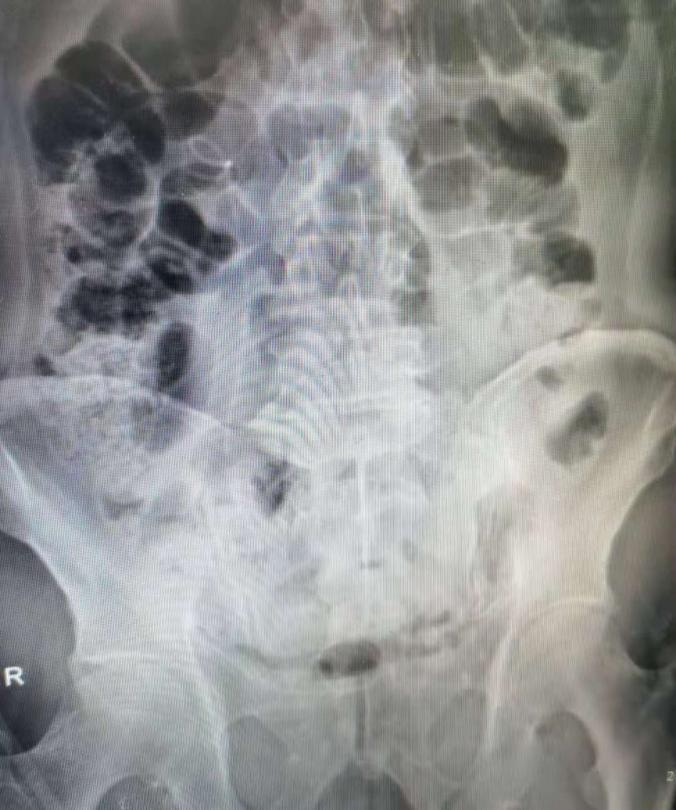

本例患者的肾下盏结石术中使用新一代摩西激光击碎后均经负压取出,手术用时30分钟,未见明显出血及感染征像,未留置常规肾造瘘管(tubeless)。术后结石送成分分析,术后1天患者下地,2天拔除尿管,复查腹部立位片未见残石,嘱患者2-3周后拔除双J管,患者术后3天已顺利出院。此例手术亦为我院首例SMP示教病例, 对第二临床医学院在泌尿外科的实习同学进行示教,使其学习了解了泌尿外科结石领域的外科技术前沿。

术后复查腹部立位片未见明显残石